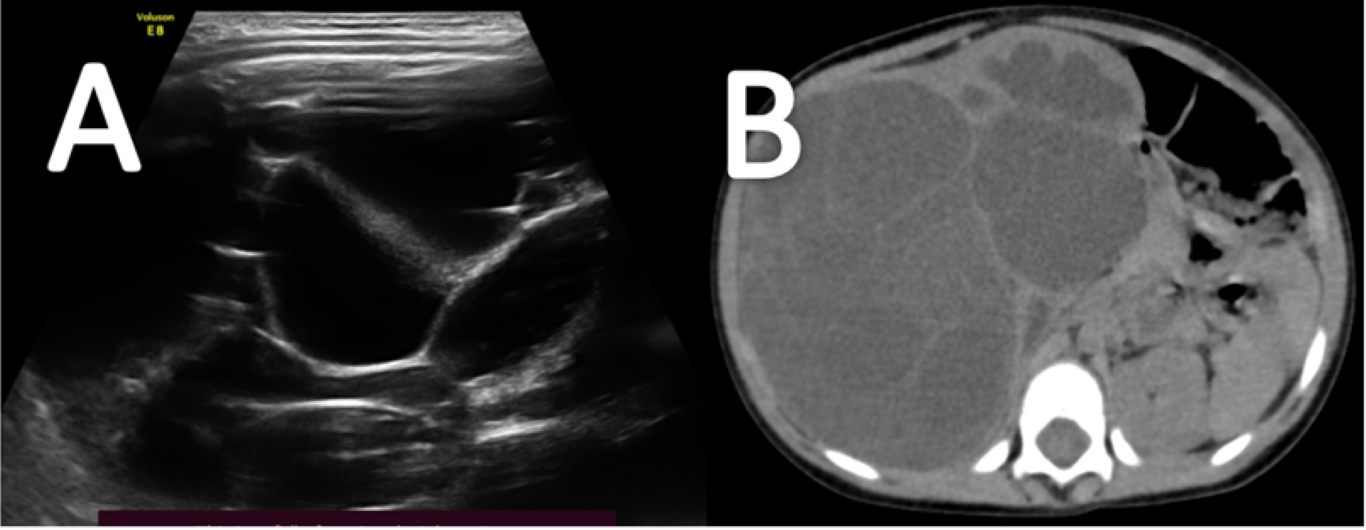

The patient was advised for USG abdomen. USG revealed a large cystic lesion with multiple thin echogenic internal septations in the right flank arising from the right kidney (Figure A). The residual right kidney was displaced medially and anteriorly. She underwent a contrast-enhanced CT scan on a 128 slice Siemens machine. On CT, there was a well defined multiloculated cystic lesion of size approx. (12.5 x10.9 x10.5) cm is seen in the right renal fossa. Multiple thick enhancing septations were observed in the lesion. A Claw sign was depicted with the adjacent right kidney suggesting an organ of origin. Residual right renal parenchyma was pushed anteromedially, showing mild hydronephrosis due to pressure effect. Renal vasculature and adjacent great vessels were unremarkable (Figure B, C, D, E). MRI was advised for better evaluation of fat planes with surrounding structures. Multiparametric and multi sequential MRI was performed over a 1.5 Tesla Siemens machine (Somatom 2014 model) using the surface coil. It revealed multiple cysts with thick septations within the lesion. The contents of the cysts appear hypointense on T1 hyperintense onT2WI. No obvious capsular breach/invasion into surrounding tissue was noted (Figure F).

Figure A- USG image illustrates a cystic lesion with multiple internal thick septations.

Figure B- Non-contrast CT axial scan shows a well-defined fluid density lesion showing internal septations in the right renal fossa region.

Figure C, D & E- Contrast-enhanced CT scan axial view (C &D) and coronal image (E) shows a well-defined multiloculated cystic lesion with thick internal septations in the right renal fossa region. Residual right renal tissue is seen displaced anteromedially. “Claw sign / Beak sign” is depicted with adjacent right kidney suggesting organ of origin.

Figure F- Non-contrast MRI abdomen T2WI shows a well-defined multiloculated cystic lesion.